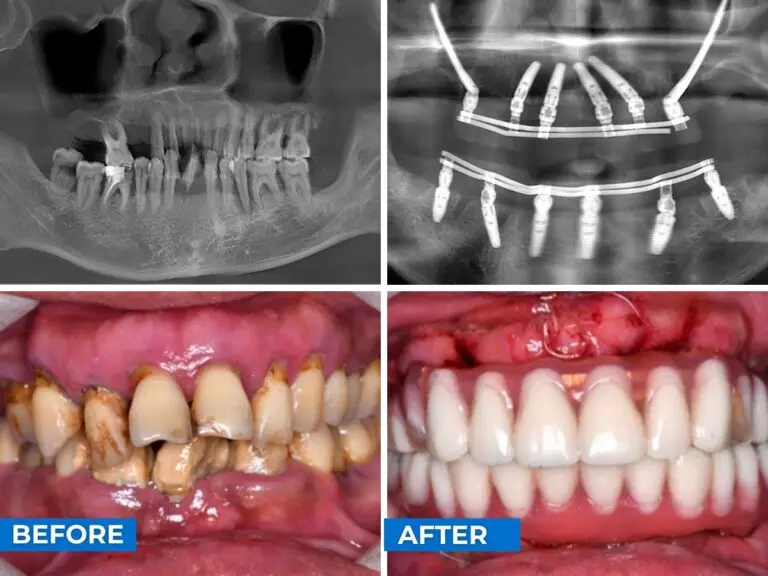

本病例展示了通过先进的种植技术实现的全口修复。 从中间、右侧和左侧角度拍摄的种植牙前后对比图片展示了种植牙如何恢复功能和自然美感,让患者重新绽放自信的笑容。